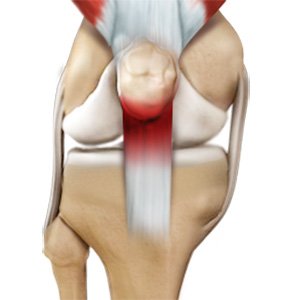

Patellar Tendinitis

Patellar tendinitis, also known as "jumper's knee", is an inflammation of the patellar tendon that connects your kneecap (patella) to your shinbone. This tendon helps in extension of the lower leg.